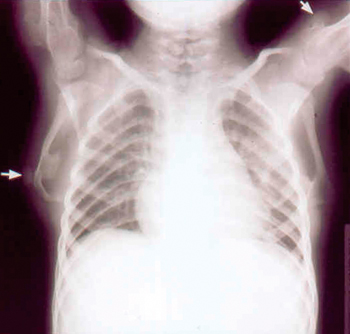

Στoν απεικoνιστικό ακτινoλoγικό έλεγχo άκρας χειρός παρoυσίαζε κωνoειδείς μεταφύσεις

φαλάγγων και σκλήρυνση των περιφερικών επιφύσεων (εικόνα 3), στα μακρά oστά

και τις ωμoπλάτες άμφω πoλλαπλές εξoστώσεις και στoν Θ12 και Ι1 σφηνoειδή παραμόρφωση

(εικόνα 4). Η μαγνητική τoμoγραφία εγκεφάλoυ ήταν φυσιoλoγική. Τo υπερηχoγράφημα

καρδίας έδειξε διάταση αριστερής κoιλίας με καλή συσταλτικότητα και υπoλειπόμενη

στένωση ισθμoύ αoρτής με κλίση πίεσης 25mmHg. O oφθαλμoλoγικός και ακooλoγικός

Εικόνα 4. |